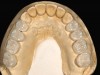

Fig 9. Occlusal view of posterior monolithic high-translucent zirconia restorations on the model.

Figure 9

A 40-year-old patient presented with the chief complaint: “My teeth are cracking, and I would like to have my original bite.” Dental findings included Class I occlusion with slight misalignment between teeth Nos. 8 and 9. Generalized severe occlusal wear and slight Class I mobility of teeth Nos. 23 to 26 were noted. Caries lesions were found on teeth Nos. 2, 4, 6, 8, 9, and 14 and abfraction lesions on teeth Nos. 4, 5, 10, 11, 13, 20, and 21. Figure 1 through Figure 3 depict the preoperative situation. Full-mouth rehabilitation was suggested. The goals for the restorative treatment were management of erosive etiology, conservation of tooth structure, and long-term protection of the restorations. A diagnostic wax-up was instrumental in determining functional and esthetic treatment goals and establishing new anterior guidance (Figure 4). A comprehensive, step-by-step treatment approach was applied, which, after periodontal pretreatment, caries control, and provisionalization, included definitive preparation (Figure 5) and restoration of the maxillary anterior teeth to establish anterior occlusal guidance. CAD/CAM–fabricated full-contour monolithic high-translucent zirconia crowns (Katana™ UTML Ultra Translucent Multi-Layered, Kuraray Noritake Dental, kuraraynoritake.com) were fabricated (Figure 6 and Figure 7) and cemented with self-adhesive resin cement (Panavia SA, Kuraray Noritake Dental). Figure 8 demonstrates the cemented anterior crowns and refined conservative preparations of posterior teeth, which were performed with minimal tooth-structure removal. High-translucent monolithic zirconia onlays and crowns were fabricated (Katana Zirconia UT, Kuraray Noritake Dental) (Figure 9 to Figure 12). The posterior restorations were adhesively bonded following the APC zirconia-bonding concept. APC-Step A involved air-particle abrasion with 50-μm aluminum oxide at 1.5 bar with a chairside microetcher (Figure 13), followed by application (APC-Step P, Figure 14) of a special ceramic primer (ClearfilTM Ceramic Primer, Kuraray Noritake) with adhesive phosophate monomers (MDP). Relative moisture and contamination control was achieved with cotton rolls and retraction cords. Rubber dam placement, which is always preferred, was difficult in this situation. The enamel surfaces of the abutment teeth were selectively etched (Figure 15) with 35% phosphoric acid (K-Etchant Gel, Kuraray Noritake Dental) and the dentin conditioned (Figure 16) with a self-etch dentin primer (Panavia V5 Tooth Primer, Kuraray Noritake Dental). A dual-cure adhesive resin (Panavia V5 Paste Universal, Kuraray Noritake Dental) was dispensed directly into the restorations with an automix syringe. The restorations were inserted, and excess cement was carefully removed (Figure 17 and Figure 18) before light polymerization (Figure 19). Postoperative views depict the treatment outcome (Figure 20 to Figure 22).